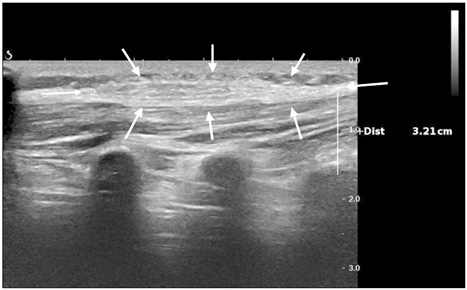

Fig. 1

Ultrasound finding of lesion (arrows).

Fig. 1 Ultrasound finding of lesion (arrows).